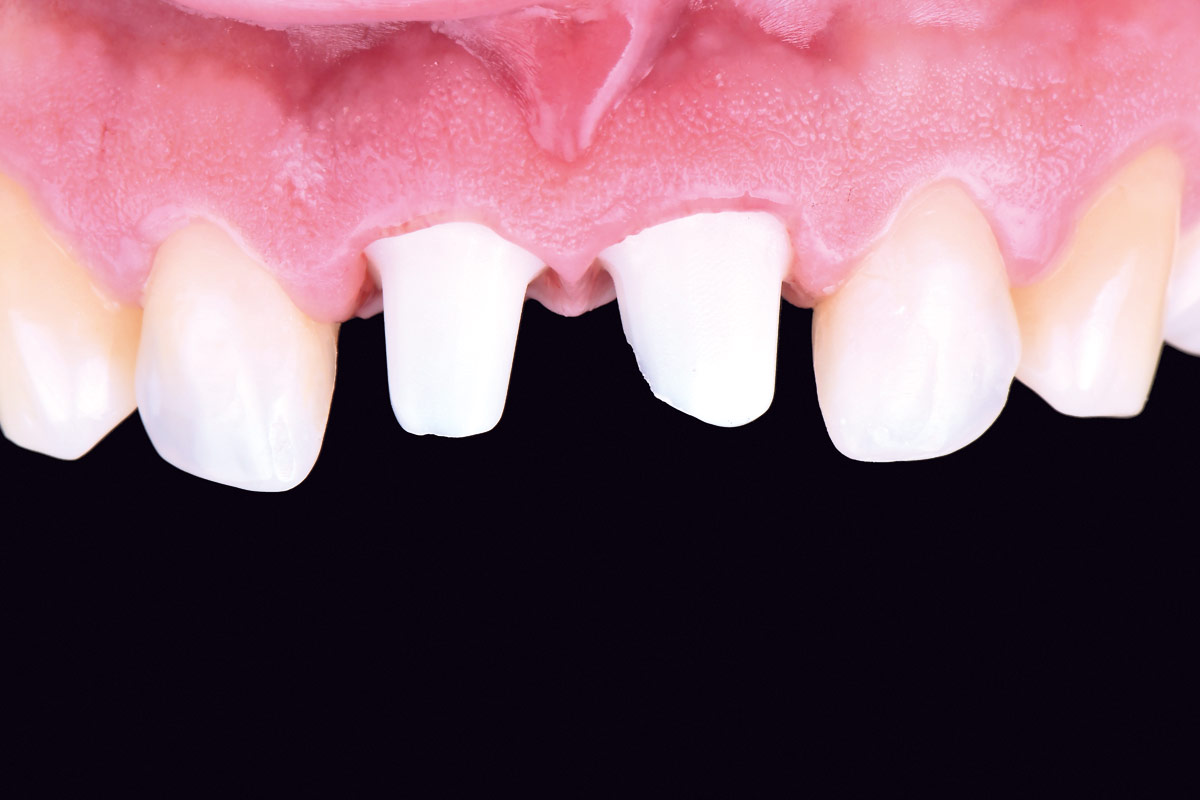

12/12 - Final clinical outcome: Two years follow-up

Treatment of a double root fracture in the aesthetic zone with cerabone® – Dr. J. M. Abarca